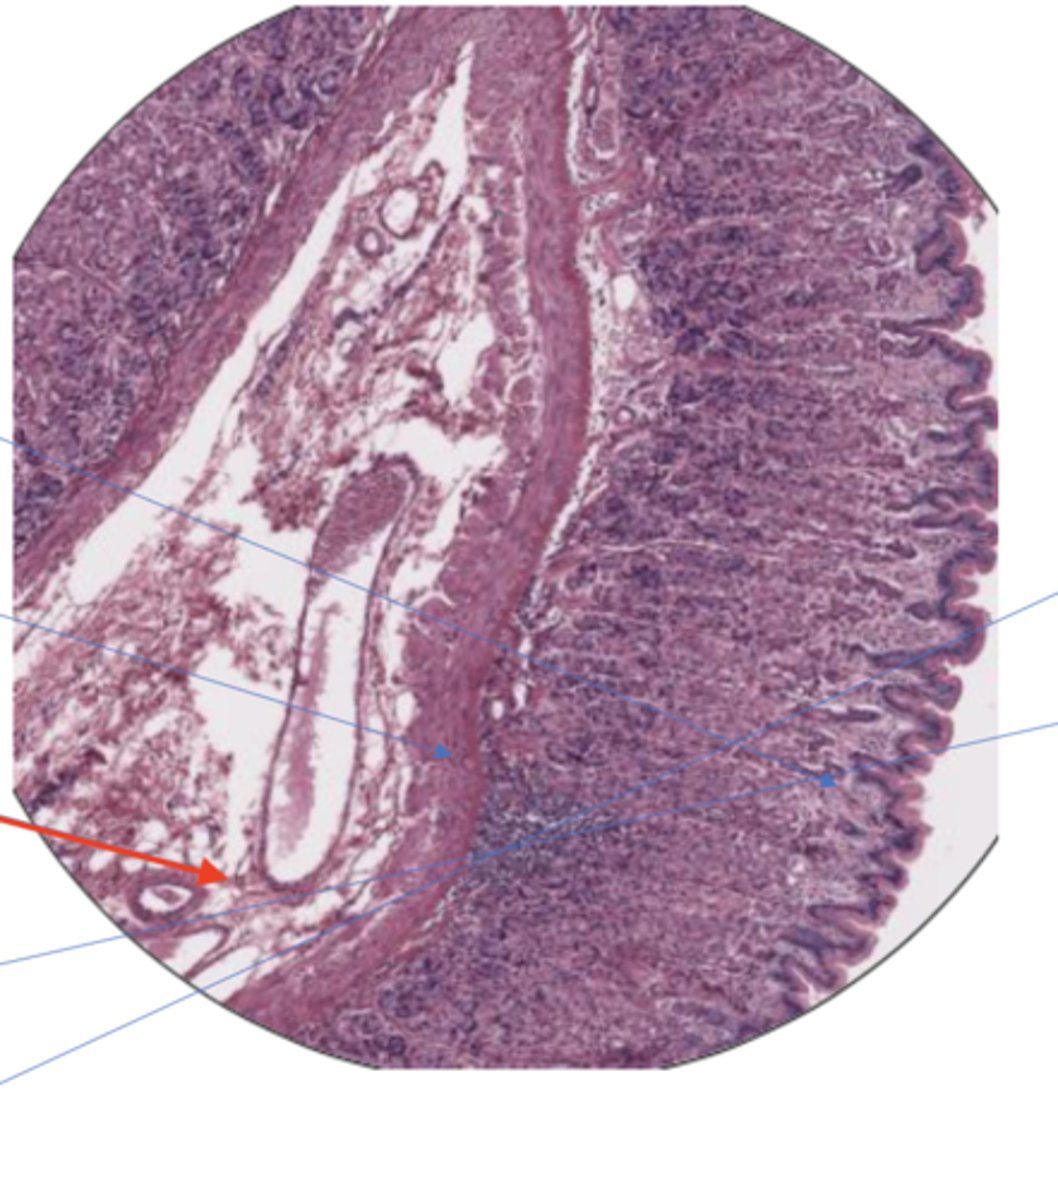

SI mucosa layer (100)

SI mucosa layer (400)